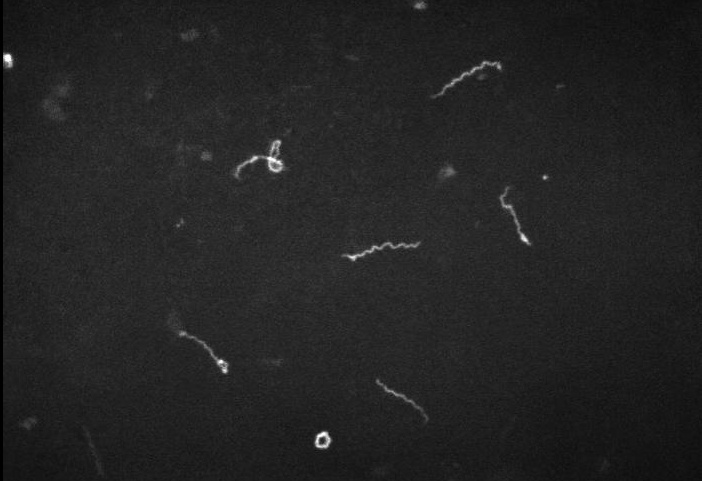

Spiral galaxy, dark microscope

"Corkscrew shaped"

spirochetes seen on darkfield microscopy

_Diagnosis of syphilis is made via direct visualization using darkfield microscopy or direct fluorescent antibody testing, and via serology. Darkfield telescope:

Darkfield microscopy: